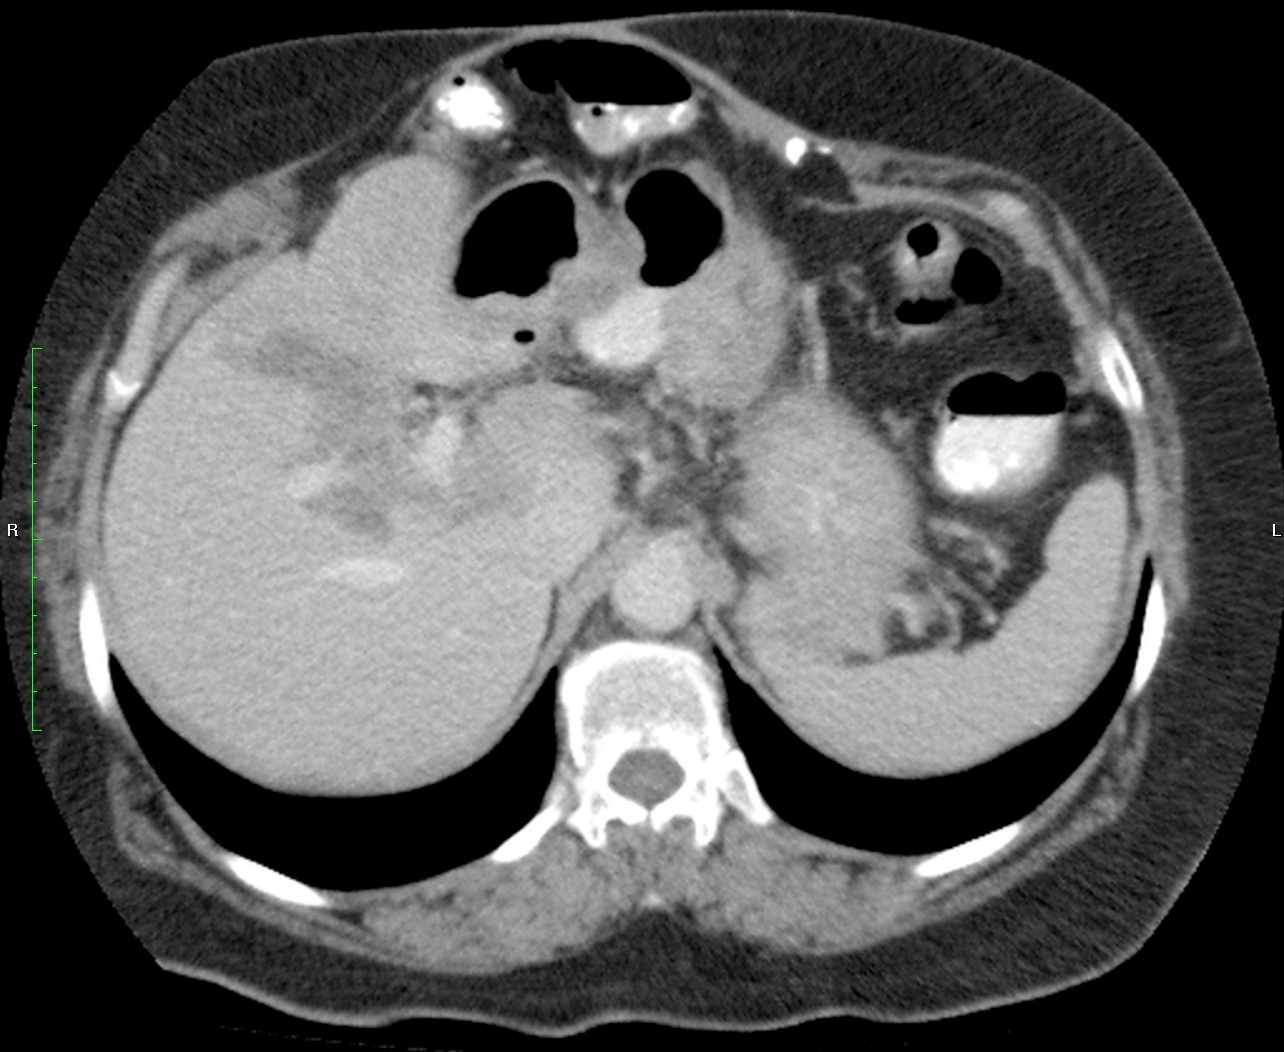

Paciente de 66 años con antecedente de pancreatitis, tomografía control.

Mujer de 57 años.

Cuadro clínico de 1 mes de evolución caracterizado por distensión abdominal e hiporexia.